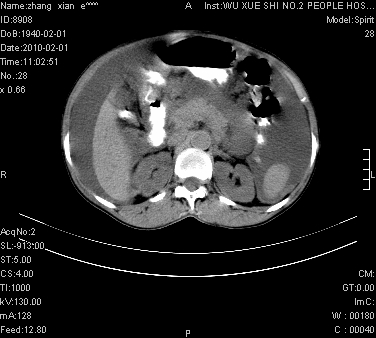

大量腹水,脾脏囊性占位,子宫颈占位,右侧腹股沟淋巴结肿大,建议+c,先查妇科。

腹盆腔大量积液,子宫增大,子宫颈增大外形不规则,内见低密度影,膀胱后壁显示不清,右腹股沟肿大淋巴结,脾脏囊性占位,子宫颈占位,子宫颈癌?建议增强。

腹盆腔大量积液,子宫增大,子宫颈增大外形不规则,内见低密度影,膀胱后壁显示不清,右腹股沟肿大淋巴结,脾脏囊性占位,子宫颈占位,子宫颈癌?建议增强。支持!

大量腹水,右肾、脾囊肿可能性大          考虑左侧附件区占位,建议增强

考虑:1、腹膜转移,大量腹水;2、脾占位性病变;3、左侧卵巢占位性病变,建议增强进一步检查。支持